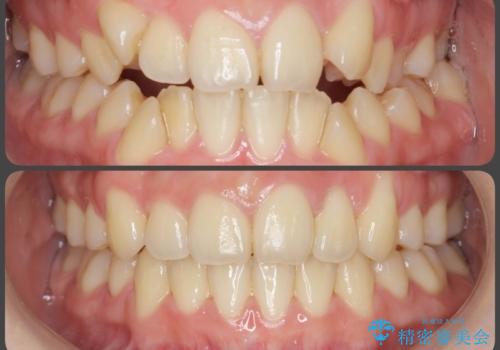

- 出っ歯のように見える前歯の角度を治したい、と矯正治療を希望され来院されました。

抜歯をせずにマウスピース矯正システムインビザラインを用いてしっかりと前歯の角度を改善していきます。

前歯の角度だけでなく内側に倒れ込んでいた奥歯もしっかり起こすことで咬合関係も理想的に仕上げています。